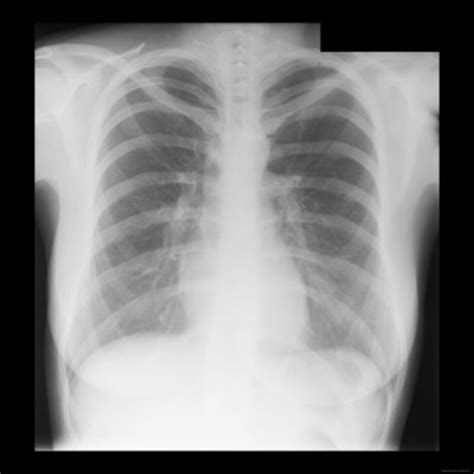

A normal lung X-ray typically shows clear lung fields with no signs of inflammation, infection, or other abnormalities. The lungs appear black due to the air they contain, while the heart and other structures appear white. The diaphragm, the muscle that separates the chest from the abdomen, is also visible and should be at a normal level.

Here are some key features of a normal lung X-ray:

• Clear lung fields with no opacities or infiltrates.

• Normal heart size and shape.

• Visible costophrenic angles (the angles where the ribs meet the diaphragm).

• No pleural effusions (fluid accumulation around the lungs).

• Normal vascular markings.